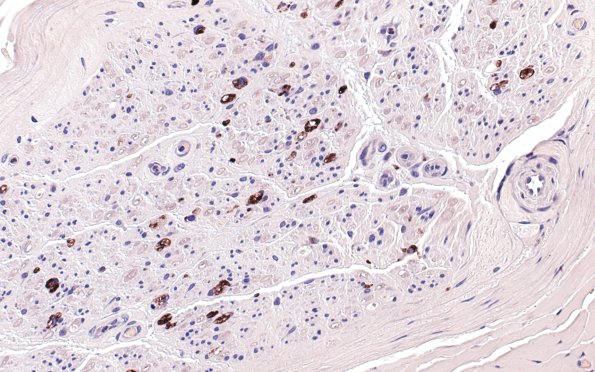

1B1 GBS, (Case 1) KP1 40X 2

This single fascicle shows numerous endoneurial macrophages. (CD68 IHC)